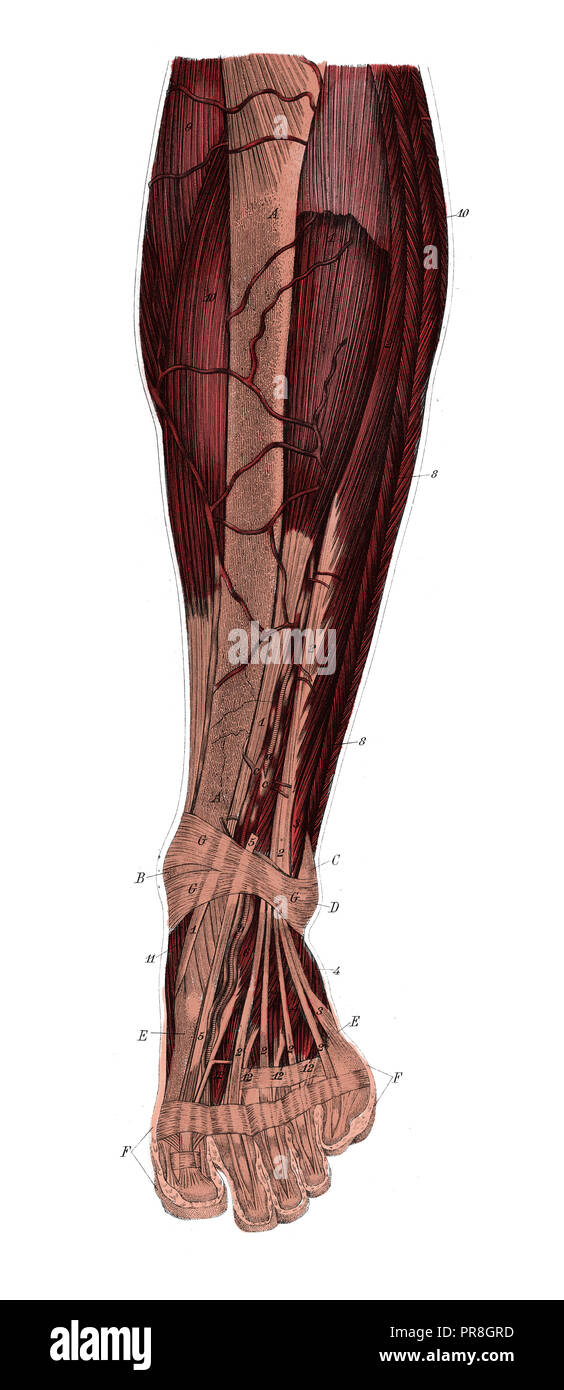

RFPR8GRD–19ème siècle illustration de la jambe gauche de l'avant après avoir enlevé la peau et le fascia. Publié dans Bilder-Atlas Conversations-Le Systematischer zum